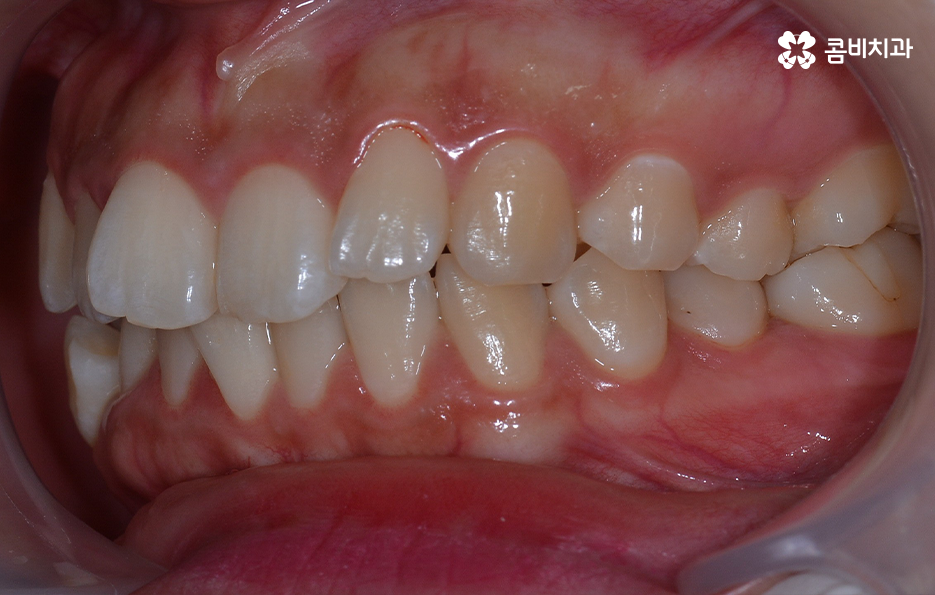

덧니는 윗니와 아랫니에 모두 있거나 앞니에 살짝 있는 수준의 덧니도 있으며 덧니가 심한 경우에는 개방교합으로 인해 입이 잘 다물어지지 않는 경우도 있기 때문에 덧니가 심한 정도에 따라서 치아교정의 계획은 세부적으로 달라질 수 있어요

덧니가 심하지 않은 경우에는 비발치로도 충분히 교정을 하는 경우도 있겠지만 덧니가 심한 경우에는 덧니 발치 교정을 통해서 치료가 진행되는 경우가 많이 있는데요. 그 이유는 치아교정의 원리를 생각하더라도 치아를 재배치하기 위해서는 기존의 치아가 움직일 공간이 필요한데 덧니는 치열이 이미 완성되고 있는 상태에서 치아가 나올 공간이 부족하여 덧니가 되는 경우가 많다는 점에서도 치아의 이동 공간을 확보하기 위한 발치가 필요할 수 있는 거예요